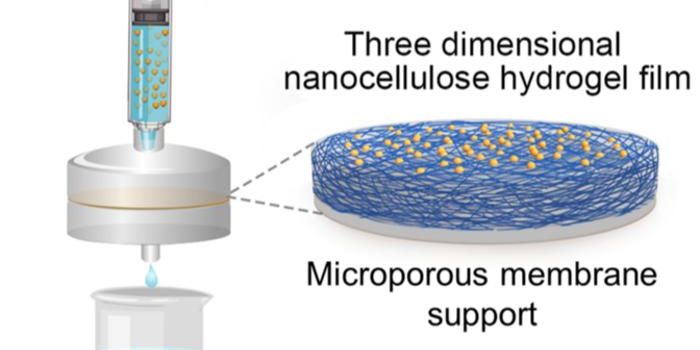

SEP 08, 2024Cell & Molecular BiologyThe human small intestine is an essential organ that helps us absorb nutrients and vitamins from food. It is an average ...

AUG 16, 2024MicrobiologyAnimal models have served as excellent models of many aspects of human biology and disease, but they cannot mimic every ...